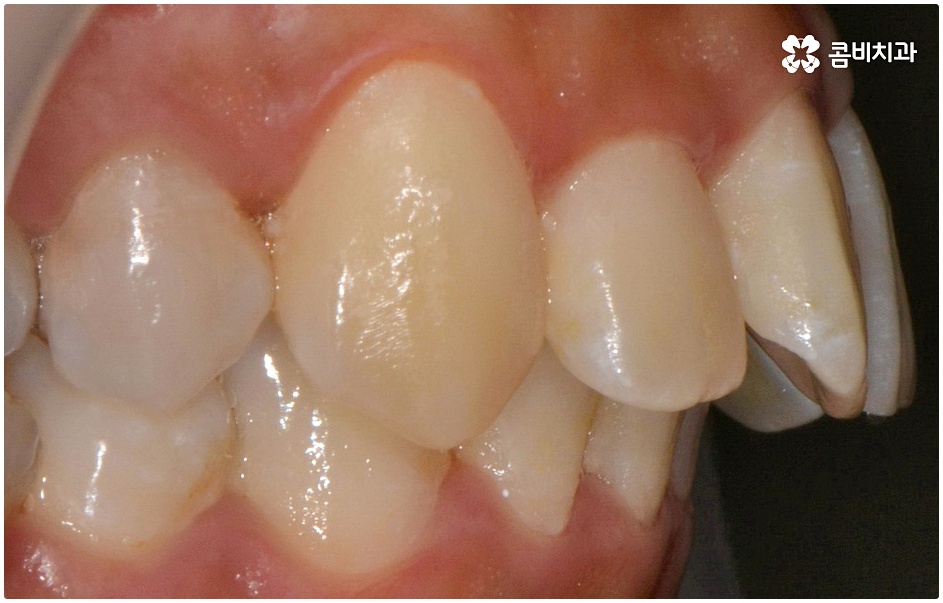

돌출입의 경우 씹기가 불편하고 입을 닫을 때 어려움이 있으며 웃을 때 부자연스러운 입 모양 및 코보다 입이 더 튀어나와 균형이 맞지 않는 옆모습에 대한 심미적인 불만족을 이유로 돌출치아교정 을 고려해 볼 수 있는데요.

돌출입에는 두 가지 경우가 있는데 먼저 치아들의 각도가 앞으로 뻗어서 돌출되는 경우와 골격 구조상 튀어나온 경우 (즉, 치아를 잡아주는 상악 치조골, 잇몸 자체가 돌출된 경우 또는 하악 턱이 뒤로 후퇴한 경우) 이렇게 나눌 수 있으며 정확한 원인을 파악하는 것이 중요하기 때문에 꼼꼼한 검진 및 면밀한 상담이 우선시 될 필요가 있어요.

치료를 위해서는 입을 안쪽으로 넣기 위한 공간을 확보해야 하므로 보통 위아래 소구치 총 4개의 치아를 발치하여 그 공간을 활용해 튀어나온 치아와 잇몸을 전체적으로 뒤로 이동시키는 방법을 사용하나 최근에는 미니스크류, 치간 삭제 등의 방법을 이용하여 비발치 교정을 진행하기도 하니 먼저 자신의 상황을 꼼꼼하게 살펴보고 부정 교합의 원인과 정도부터 정확하게 파악하는 것이 필요한 거에요.